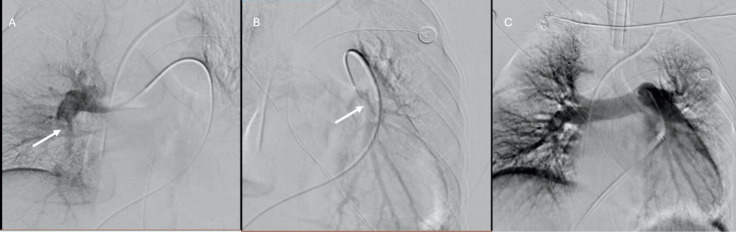

Case presentation: Case 1: A 39-year-old pregnant woman at 36 weeks and 5 days of gestation with central placenta previa was admitted due to antepartum hemorrhage. She developed convulsions and cardiac arrest during a cesarean section, requiring cardiopulmonary resuscitation. Laboratory tests revealed severe anemia, thrombocytopenia, coagulopathy, severe acidosis, and myocardial injury. Bedside echocardiography and CT scan identified high-risk pulmonary embolisms. Intensive care included VA-ECMO, CRRT, transcatheter arterial embolization, and mechanical thrombectomy. Histopathology confirmed amniotic fluid components making up the emboli. Case 2: A 31-year-old female was transferred following a cesarean section for central placenta previa complicated by severe hemorrhage, cardiac arrest, and pulmonary embolism. Laboratory results showed severe anemia, thrombocytopenia, significant coagulopathy, myocardial injury, and hepatic injury. Histopathology confirmed amniotic components in the embolism. Management involved extensive blood transfusions, and pulmonary thromboendarterectomy. She was discharged in improved condition.